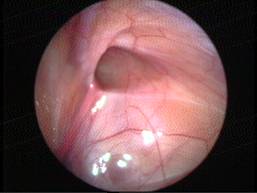

Can this operation done by laparoscopy?

Operation in hernia involves closing of the open passage through which the testis has come down. This can be done from outside as in open surgery or from inside by laparoscopy. If your child has got a hernia on one side, there is a 15 – 25 % chance that he / she may develop a hernia on the opposite side at a later date. With the help of laparoscopy we are able to look at the opposite side to see if the passage is open on that side as well. This can be closed at the same sitting if you wish to. Recovery from surgery, timing of surgery and discharge from hospital are the similar for open surgery and laparoscopic surgery.

However, it is important to note that an open passage does not always mean that your child will get a hernia. There is no harm in opting for a second surgery later if your child at all develops a hernia on the opposite side.

Laparoscopic repairs have a slightly higher chance of recurrence (i.e. the hernia coming back again) as compared to open hernias. You can discuss the pros and cons in details with your doctor when you come for consultation.